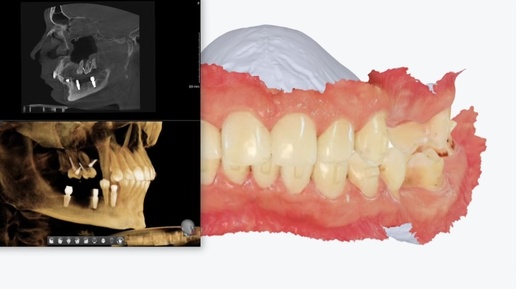

Под красивой металлокерамической "подковой" оказалась труха - тотальная имплантация с одномоментной нагрузкой, 6 имплантатов на 1 челюсть

Если вы посмотрите на фото "до", то вряд ли подумаете, что нам пришлось удалить все зубы на верхней челюсти... Однако, вся верхняя челюсть состоит из сплошной подковы из металлокерамики. Это, само по себе, допустимо, но не всегда и не везде. Снизу тоже МК, но не подкова. Пациентка пришла с жалобами на боль, неприятный запах, скол керамики. Она уже понимала, что её ожидает впереди. Первое, что бросилось в глаза - конструкция на верхней челюсти справа. Мост от первого резца до седьмого зуба - 5 единиц без опоры в виде корней, имплантатов: Внимание - пять единиц подряд висят в воздухе! Зубы 1...